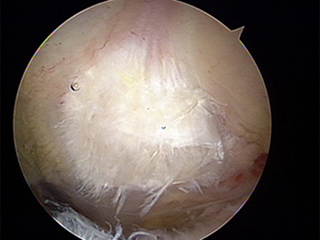

견봉성형술 후